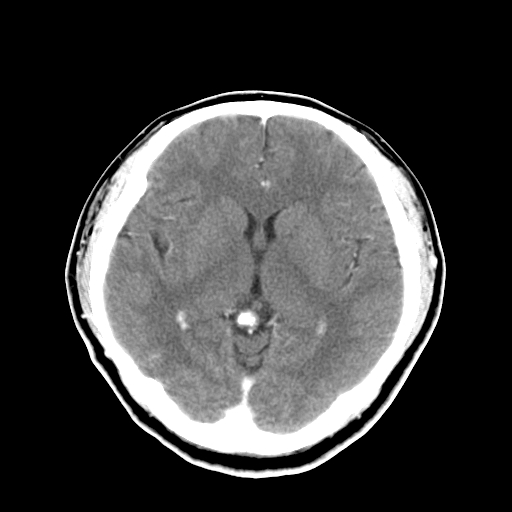

标题: CT16447B:(续)增强扫描图像。

患者今日做ct增强检查,现补传增强扫描图像。

松果体钙癍增大,无其他改变,定不了性

一般认为大于1cm为异常。